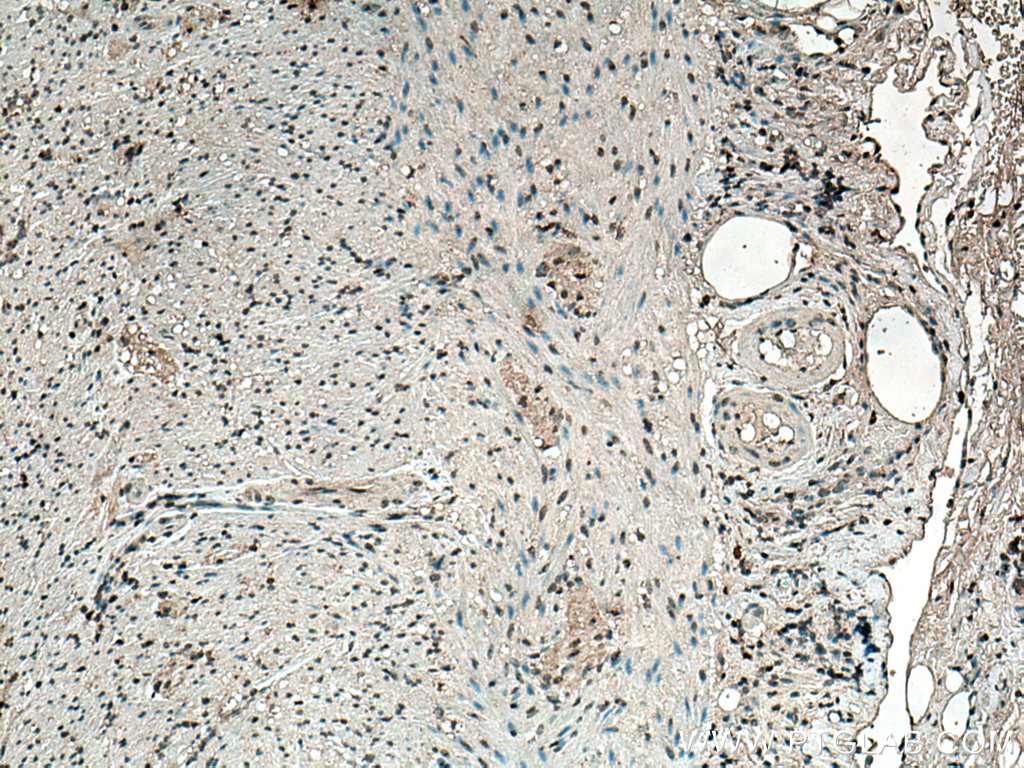

| Positive IHC detected in | rat brain tissue, human appendicitis tissue Note: suggested antigen retrieval with TE buffer pH 9.0; (*) Alternatively, antigen retrieval may be performed with citrate buffer pH 6.0 |

| Immunohistochemistry (IHC) | IHC : 1:1000-1:8000 |